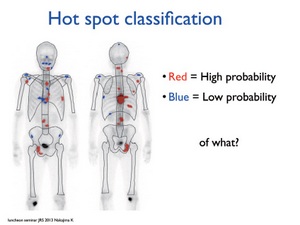

第15回日本核医学会春季大会ランチョンセミナー 骨転移の診断 治療